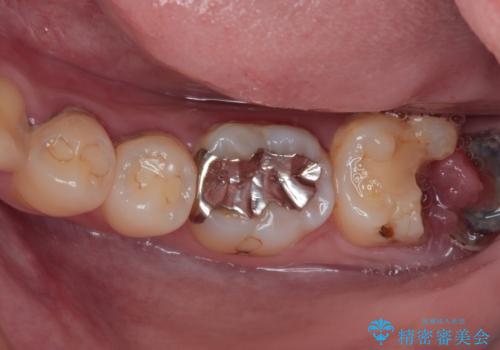

まずは歯石除去とブラッシング方法などの衛生指導を徹底的に行って口腔内環境を改善し、汚れの溜まりやすくなっている親知らずは全て抜去することとしました。

その後、歯根だけとなっている歯はインプラントに、神経組織の失活している歯は根管治療を行い、いずれもオールセラミッククラウンにて補綴治療を行うこととしました。